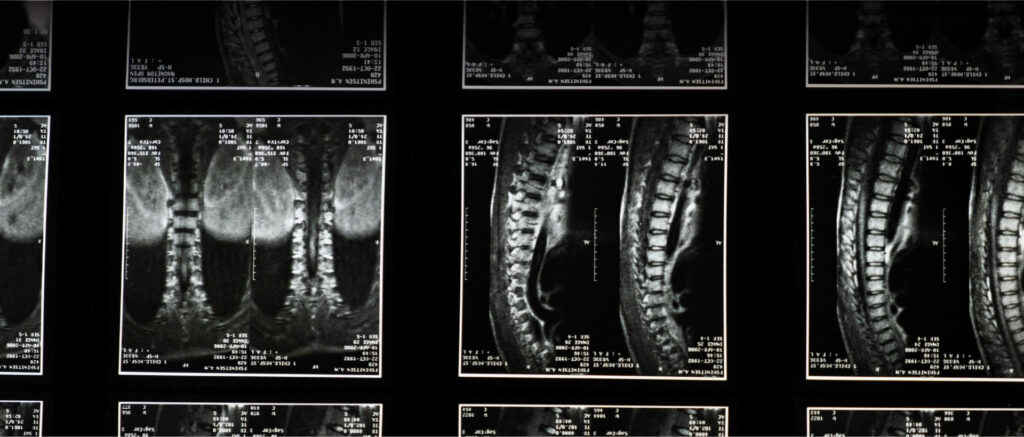

A coluna vertebral é a estrutura central do esqueleto humano, responsável por sustentar o corpo, permitir movimentos e proteger a medula espinhal. Composta por 33 vértebras distribuídas entre as regiões cervical, torácica, lombar, sacral e coccígea, ela forma um eixo flexível e resistente, essencial para a postura e a locomoção. Entre as vértebras, os discos intervertebrais atuam como amortecedores, reduzindo o impacto e garantindo a mobilidade.

Além de sua função estrutural, a coluna vertebral desempenha um papel fundamental no sistema nervoso, pois abriga e protege a medula espinhal, que transmite sinais entre o cérebro e o restante do corpo. Qualquer alteração ou lesão nessa região pode causar dores, limitações de movimento e até déficits neurológicos, tornando essencial o cuidado com a saúde da coluna por meio de postura adequada, atividade física e acompanhamento médico quando necessário.

A decisão por cirurgia é feita com base em critérios clínicos, exames de imagem e avaliação funcional do paciente. Veja as principais opções: